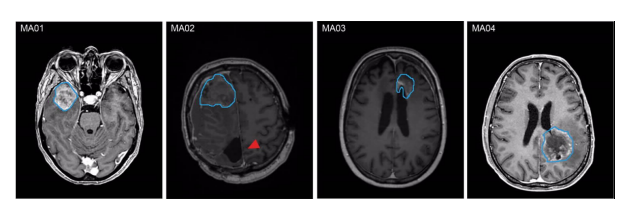

MA01-03為WHO Ⅳ級(jí)IDH野生型膠質(zhì)母細(xì)胞瘤;MA04為WHO Ⅳ級(jí)星形細(xì)胞瘤IDH突變體。

圖1 不同患者M(jìn)RI